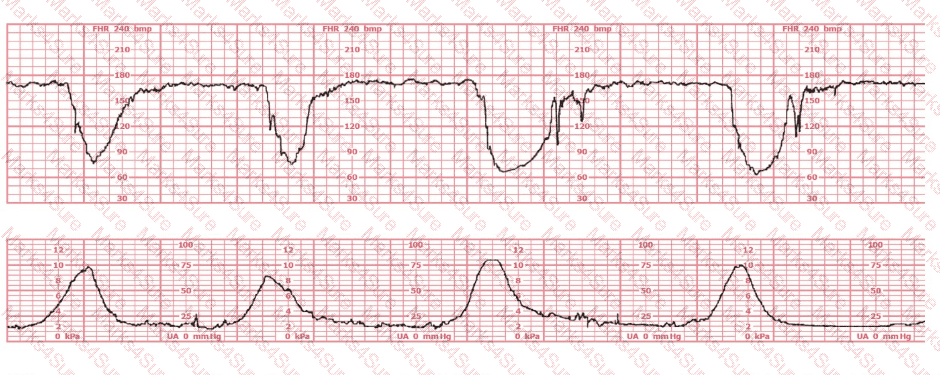

The decelerations seen in the fetal monitoring tracing shown are best described as:

A nulliparous woman at term presents with leaking fluid. Rupture of membranes confirmed. After 6 hours she is completely dilated, +2 station, has been pushing 2 hours with oxytocin at 10 mU/min. The fetal tracing is shown. What is the next step in management?